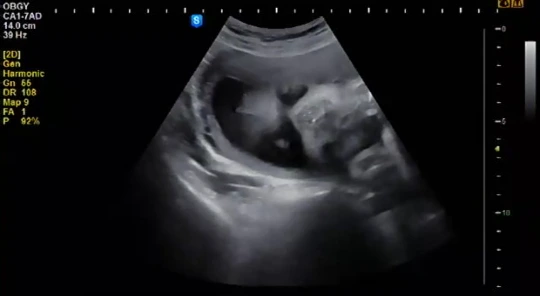

초음파로 확인했을 때 아기는 이미 2달쯤 자란 상태였다 초음파 사진을 들고 병원에서 털래털래 나오는 그 남자와 나는 알 수 없는 감정이었다. 분명 인터넷 어딘가에서는 기쁨과 벅참이 공존하는 순간이라 알려줬었는데 현실은 알 수 없는 암담함뿐이었다. 최근에 그 감정을 무기징역, 종신형이라는 단어로 적절히 표현할 수 있다는 것을 알게 되었는데, 무튼 나는 무기징역이다. 세 번째 달이 지나고 병원에 갔다. 아기를 지켜보러 2주에 한번. 매달 병원에 가야 한다는 사실도 너무 귀찮을 뿐이었다. 안 가도 아무 일 없지 않을까? 요란 떨고 싶지 않았다. 인스타 속의 많은 임신한 여자들은 아기 초음파 사진을 올려두고 감동에 벅차오르는 멘트를 적는 듯했다. 예비 워킹맘인 나는 감동을 나눌 시간 따윈 없었고 뱃속의 아기에게 너무나 무심한 여자였다. 내 마음이 그래서 그랬는지 뿌옇게 보이는 초음파 속의 아기는 한참을 얼굴조차 보여주지 않았다. 남들은 쉽게 본다는 그 얼굴을 한참이나 지난 뒤에 보았는데 선생님이 그랬다

부인과에서 산부인과로 이제 그만, 제발 가라는 명이 떨어졌고 나는 산부인과에 가면 제일 먼저 입술이 두꺼운지 다리가 짧은 건 아닌지 확인하기 위해 3d 초음파를 할 참이었다. 인사를 하고 나와서 선생님이 추천해준 가락동의 산부인과로 갔다. 원장님은 오늘은 전체적인 검사를 하고 다음 주에 3d 초음파를 하라고 했다. 성별도 안 알려준다. 딸인지 아들인지 안다고 대수롭지않은 말투로 말해보았는데 안 넘어간다. 누군가 대신 꿔준 태몽과 전 원장님이 지긋이 알려준 성별은 너무나 만족스러웠으나 20주가 지나면서 혹시나 바뀔 수도 있단다. 계속 떠보았으나 원장님은 결단코 안 알려줄 셈이었다. 다음 주를 기약하고 병원에서 나왔다. 작은 동네 부인과의 외로운 임산부였던 나는 21세기에 8개월이 될 때까지 아기 얼굴도 모르는 뒤쳐지는 엄마가 된 것이었다. 이곳은 서울의 입시 학원 같은 곳이었다. 저 산골에서 상경한 학생처럼 모르는 것 투성이었다. 심지어 나라에서 하는 기본 검사도 안 받은 것들이 있었으니 말이다. 나는 심기일전하는 심정으로 다음 예약을 기다렸다. 병원 예약일을 기다리다니. 처음 있는 일이었다.